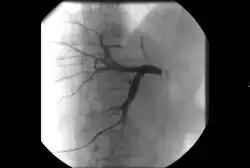

• Transarterial chemoembolization (TACE): Injection of a chemotherapy agent often with microparticles through a catheter into arteries feeding a tumor that both delivers chemotherapy and blocks the blood supply to the tumor to cause cell death[65]

TACE

• Can be performed in different ways:

• Conventional transarterial chemoembolization (cTACE): Injection of lipiodol with high dose chemotherapy with or without microparticles directly into the tumor-feeding arteries.[66]

• Drug eluting bead transarterial chemoembolization (DEB-TACE): delivery of microparticles that are themselves loaded with the chemotherapy agent—typically doxorubicin or irinotecan.